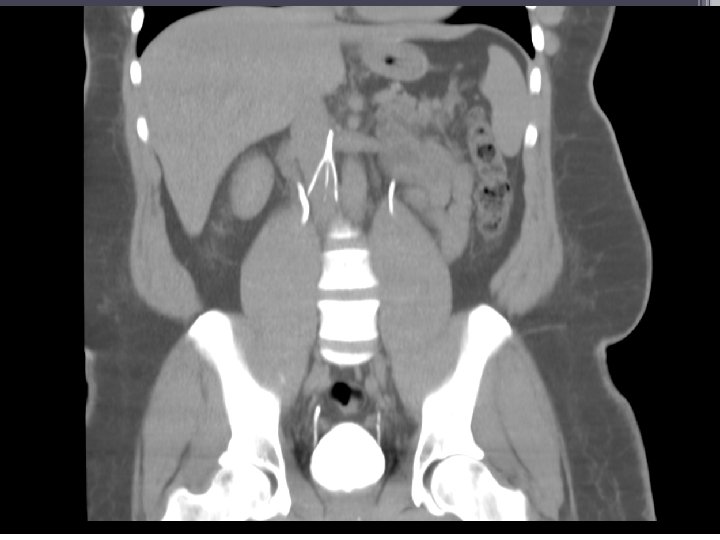

57 YO male with chronic abdominal pain radiating to the back; Greenfield filter placed over 5 years prior

Pre-Retrieval Workup • • • Is the problem solved? Duplex study of existing DVT Discussion with PMD Activity level Discussion of risk/benefit CT/MR if necessary ▫ IVC patency ▫ Filter penetration ▫ Filter tilt and adherence